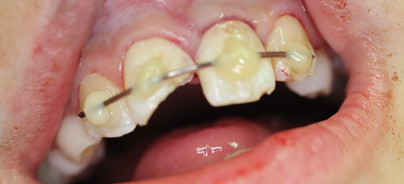

Extraoral waren Schürfwunden an Stirn und Nase zu erkennen. Intraoral imponierte die mit einem Blutkoagulum gefüllte Alveole Regio 21 sowie der abgebrochene Zahn 11. Es lagen keine Weichteilverletzungen vor und es gab keine klinischen Anzeichen für knöcherne Frakturen, auch röntgenologisch waren keine knöchernen Frakturzeichen zu erkennen (Abb. 1). Der Versuch der Erhaltung des Zahnes 21 sollte durch Replantation, Schienung und anschließende endodontische Versorgung erfolgen. An Zahn 11 war eine dentinadhäsive Rekonstruktion mit Komposit geplant.

Am Tag des Unfalls wurde die Wurzeloberfläche des avulsierten Zahnes zunächst mit NaCl abgespült (Abb. 2). Die knöchern völlig intakte Alveole wurde ebenfalls mit NaCl gespült. Dabei ist darauf zu achten, dass das in der Alveole entstandene Koagulum vorsichtig und vollständig ausgespült wird, ohne dass die parodontalen ­Fasern und Zementoblasten verletzt werden (Abb. 3). Anschließend wurde der avulsierte Zahn 21 mittels einer Frontzahnzange in seine Alveole replantiert und mit ­einer Draht-Kunststoff-Schiene geschient (Abb. 4). Am vitalen frakturierten Zahn 11 wurden die pulpanahen Bereiche mit einem Kalziumhydroxidpräparat abgedeckt und dieses provisorisch mit einem Flow fixiert. Anschließend wurde eine Röntgenaufnahme zur Kontrolle der Replantation angefertigt (Abb. 5). Es wurde ein Rezept über ein Analgetikum sowie ein Antibiotikum ausgestellt. Für den folgenden Tag wurde ein Kontrolltermin in der Oralchirurgie sowie der erste Termin in der Zahnarztpraxis für Kinder bei Dr. Christina Masuck vereinbart.